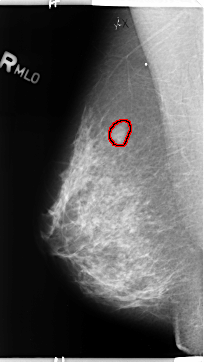

B_3142_1.RIGHT_MLO

FILE: B_3142_1.RIGHT_MLO.OVERLAY

TOTAL_ABNORMALITIES 1

ABNORMALITY 1

LESION_TYPE MASS SHAPE OVAL MARGINS CIRCUMSCRIBED-OBSCURED-ILL_DEFINED

ASSESSMENT 4

SUBTLETY 3

PATHOLOGY BENIGN

TOTAL_OUTLINES 1

BOUNDARY